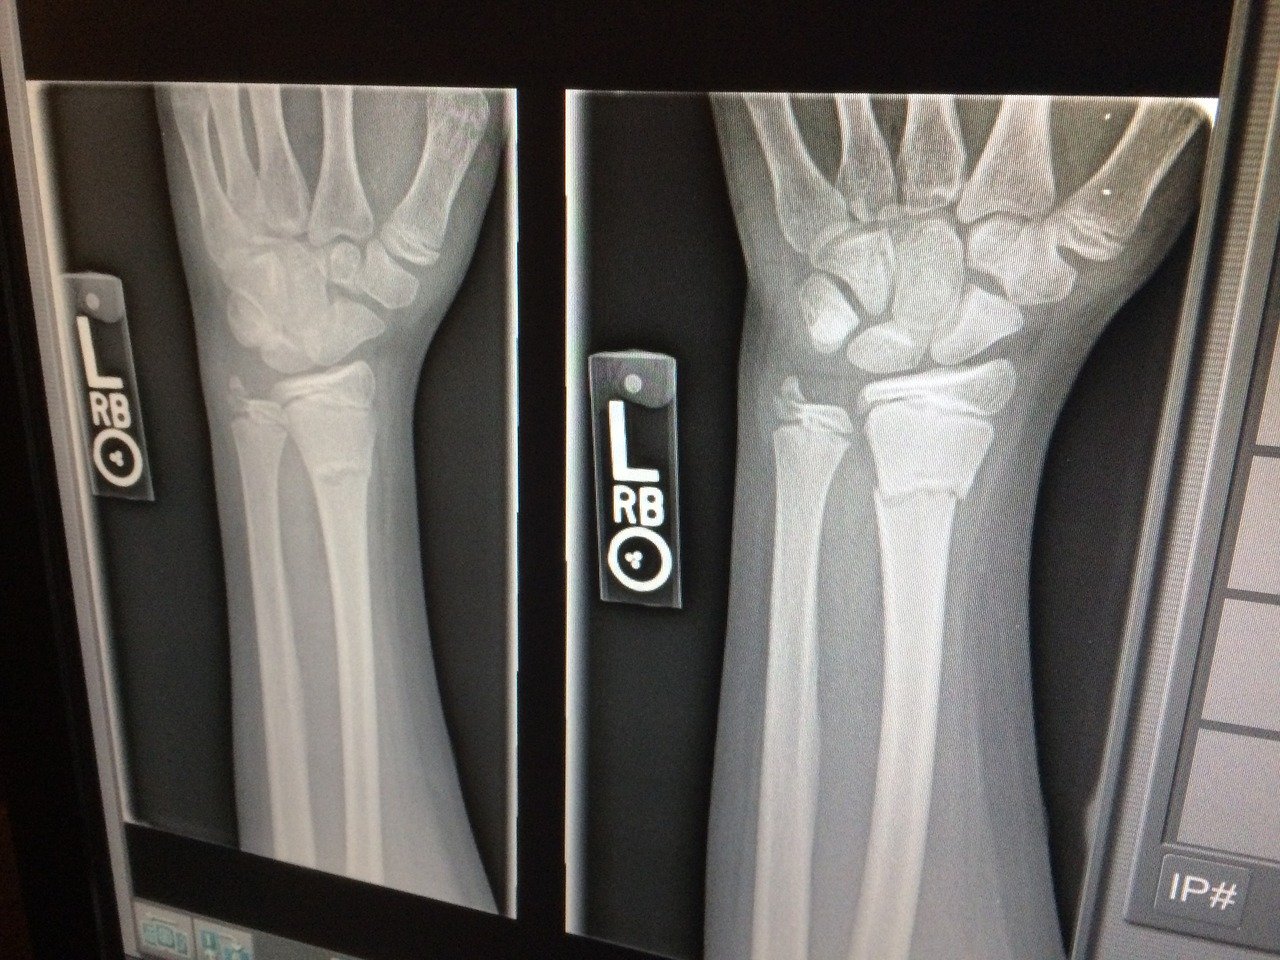

Meanwhile, U.S. researchers have taken their first look at some U.S. FDA-approved products that attempt to assess neurological, pulmonary and musculoskeletal trauma indications. In a study in the journal Emergency Radiology (2020), the authors conclude that "the ability to triage patients and attend to acute processes such as intracranial hemorrhage, pneumothorax, and pulmonary embolism can largely benefit the health care system, improve patient care, and reduce costs."

xray

Artificial intelligence is seen as having a lot of potential, especially in radiology. Deep learning, in particular, has shown results in analyzing medical images to identify diseases such as breast cancer, lung cancer, and glaucoma at least as accurately as human specialists. credit: pixabay